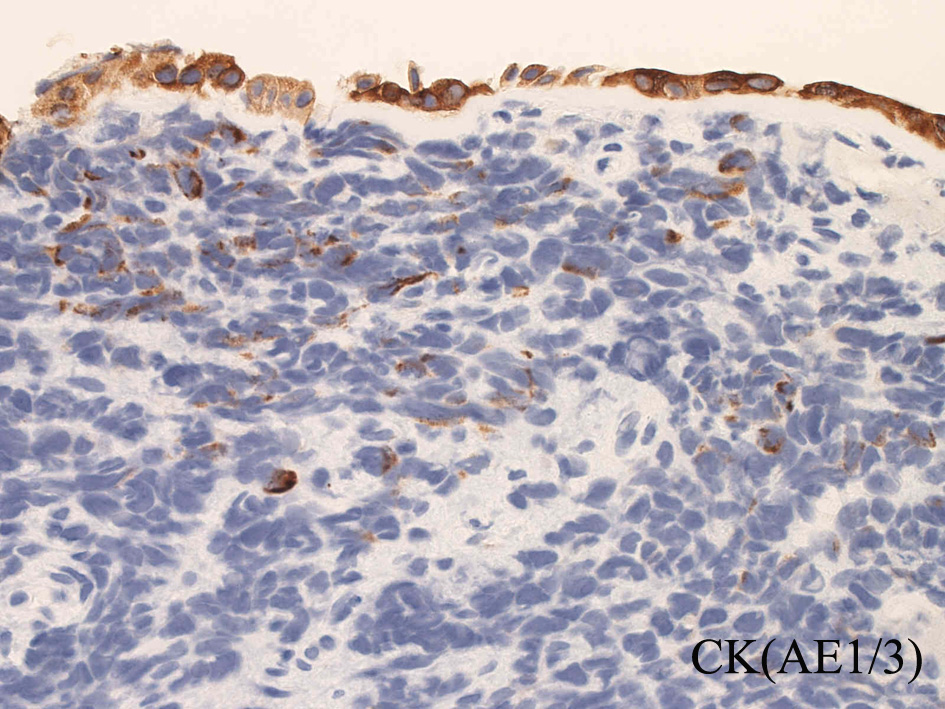

免疫染色

DesminDesminmyogenin

small round cell tumorの中でrhabdomyosarcomaは腫瘍細胞に種々の抗原が陽性となるため診断を誤ることがあり注意が必要である*1

*1 Bahrami A, et al., Aberrant expression of epithelial and neuroendocrine markers in alveolar rhabdomyosarcoma: a potentially serious diagnostic pitfall. Mod Pathol. 2008 Jul;21(7):795-806. Epub 2008 May 16. PMID:1848799199